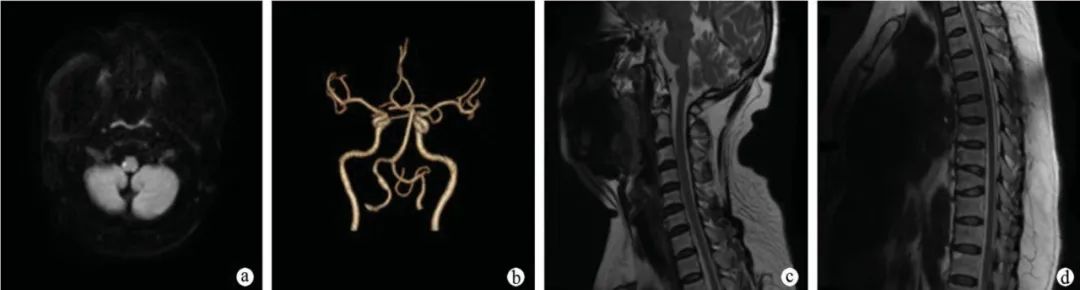

病例二

患者,女,48 岁,因头晕、恶心、呕吐 1 天入院。既往无高血压、糖尿病史。 神经系统查体:左侧 T8 以下痛觉减退,余未见异常。

a:头颅 MRI 提示右侧延髓外侧部 DWI 序列像可见一类圆形高信号病灶;b:头颈部 CTA 提示右侧椎动脉 V4 段粗细不均,局部管腔扩张;c:颈段脊髓 MRI 未见明显异常;d:胸段脊髓 MRI 未见明显异常。